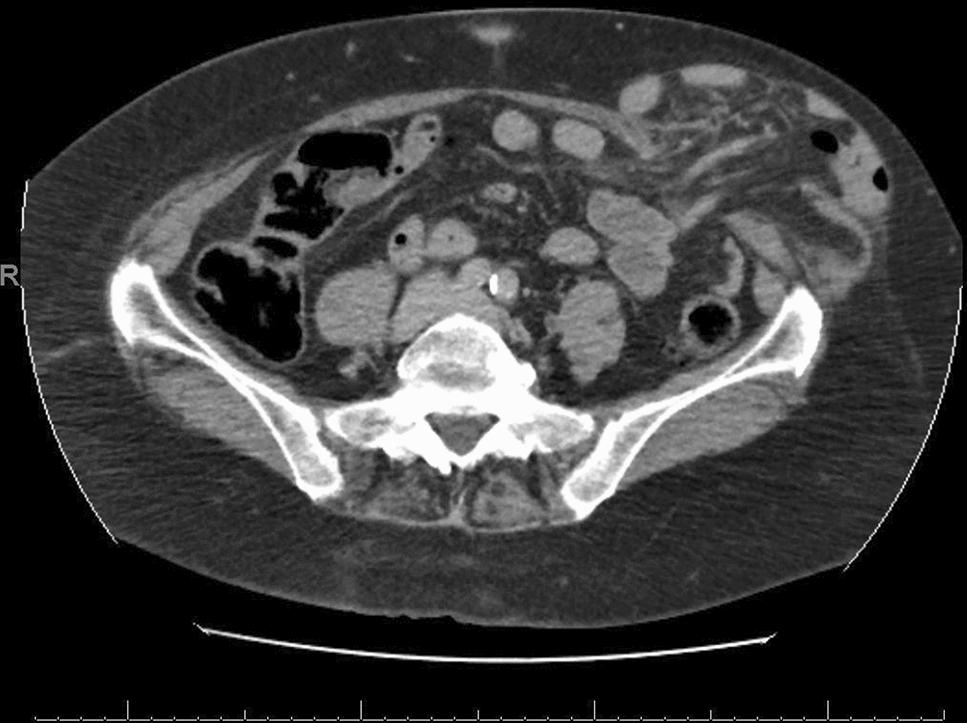

• Figs. 4,5: CT—scan of selected spigelian hernias

Fig. 4

CT-Scan of left spigelian Hernia (Foto

© U. Volmer)

Bild vergrößern

Fig. 5

CT-Scan of right spigelian Hernia (Foto